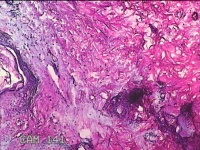

左侧腋下结节

性别

女

年龄

46岁

临床诊断

皮下结节

一般病史

发现左侧腋下一结节1周,伴局部隐痛不适,无发热。

标本名称

大体所见

灰白暗红色组织1.8x1.3x0.3cm一块,表面带梭形皮肤1.8x0.5cm,皮下见结节1.2x0.8cm,切开结节呈实性,切面灰白淡黄色,质软。

图1

炎症性病变。